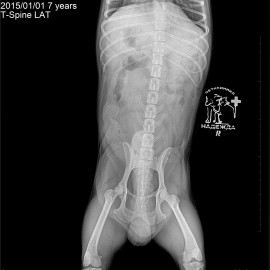

Наш пациент собака породы цвергпинчер по кличке Вальмонт.

Обратились с жалобами на нарушение опороспособности на задние лапы.

После проведённых неврологических тестов и рентгенологического исследования был поставлен предварительный диагноз: болезнь межпозвонкового диска. Было назначено проведение магнитно-резонансной томографии, после которой был поставлен точный диагноз: экструзия межпозвонкового диска на уровне TH12 - TH13 (12 -13 позвонков грудного отдела).

Снимки во время исследования пациента.